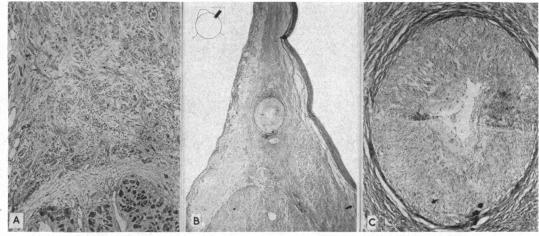

There is a remarkable remnant of primitive fibres persisting at the sino-auricular junction in all mammalian hearts. These fibres are in close connection with the vagus and sympathetic nerves, and have a special arterial supply; in them the dominating rhythm of the heart is believed to normally arise. Keith and Flack, 1907.

在所有哺乳动物的心脏中,原始纤维的显著残余部分持续存在于窦房交界处。这些纤维与迷走神经和交感神经紧密相连,并有特殊的动脉供应;人们认为心脏的主导节律通常起源于此。基思和弗莱克,1907年。